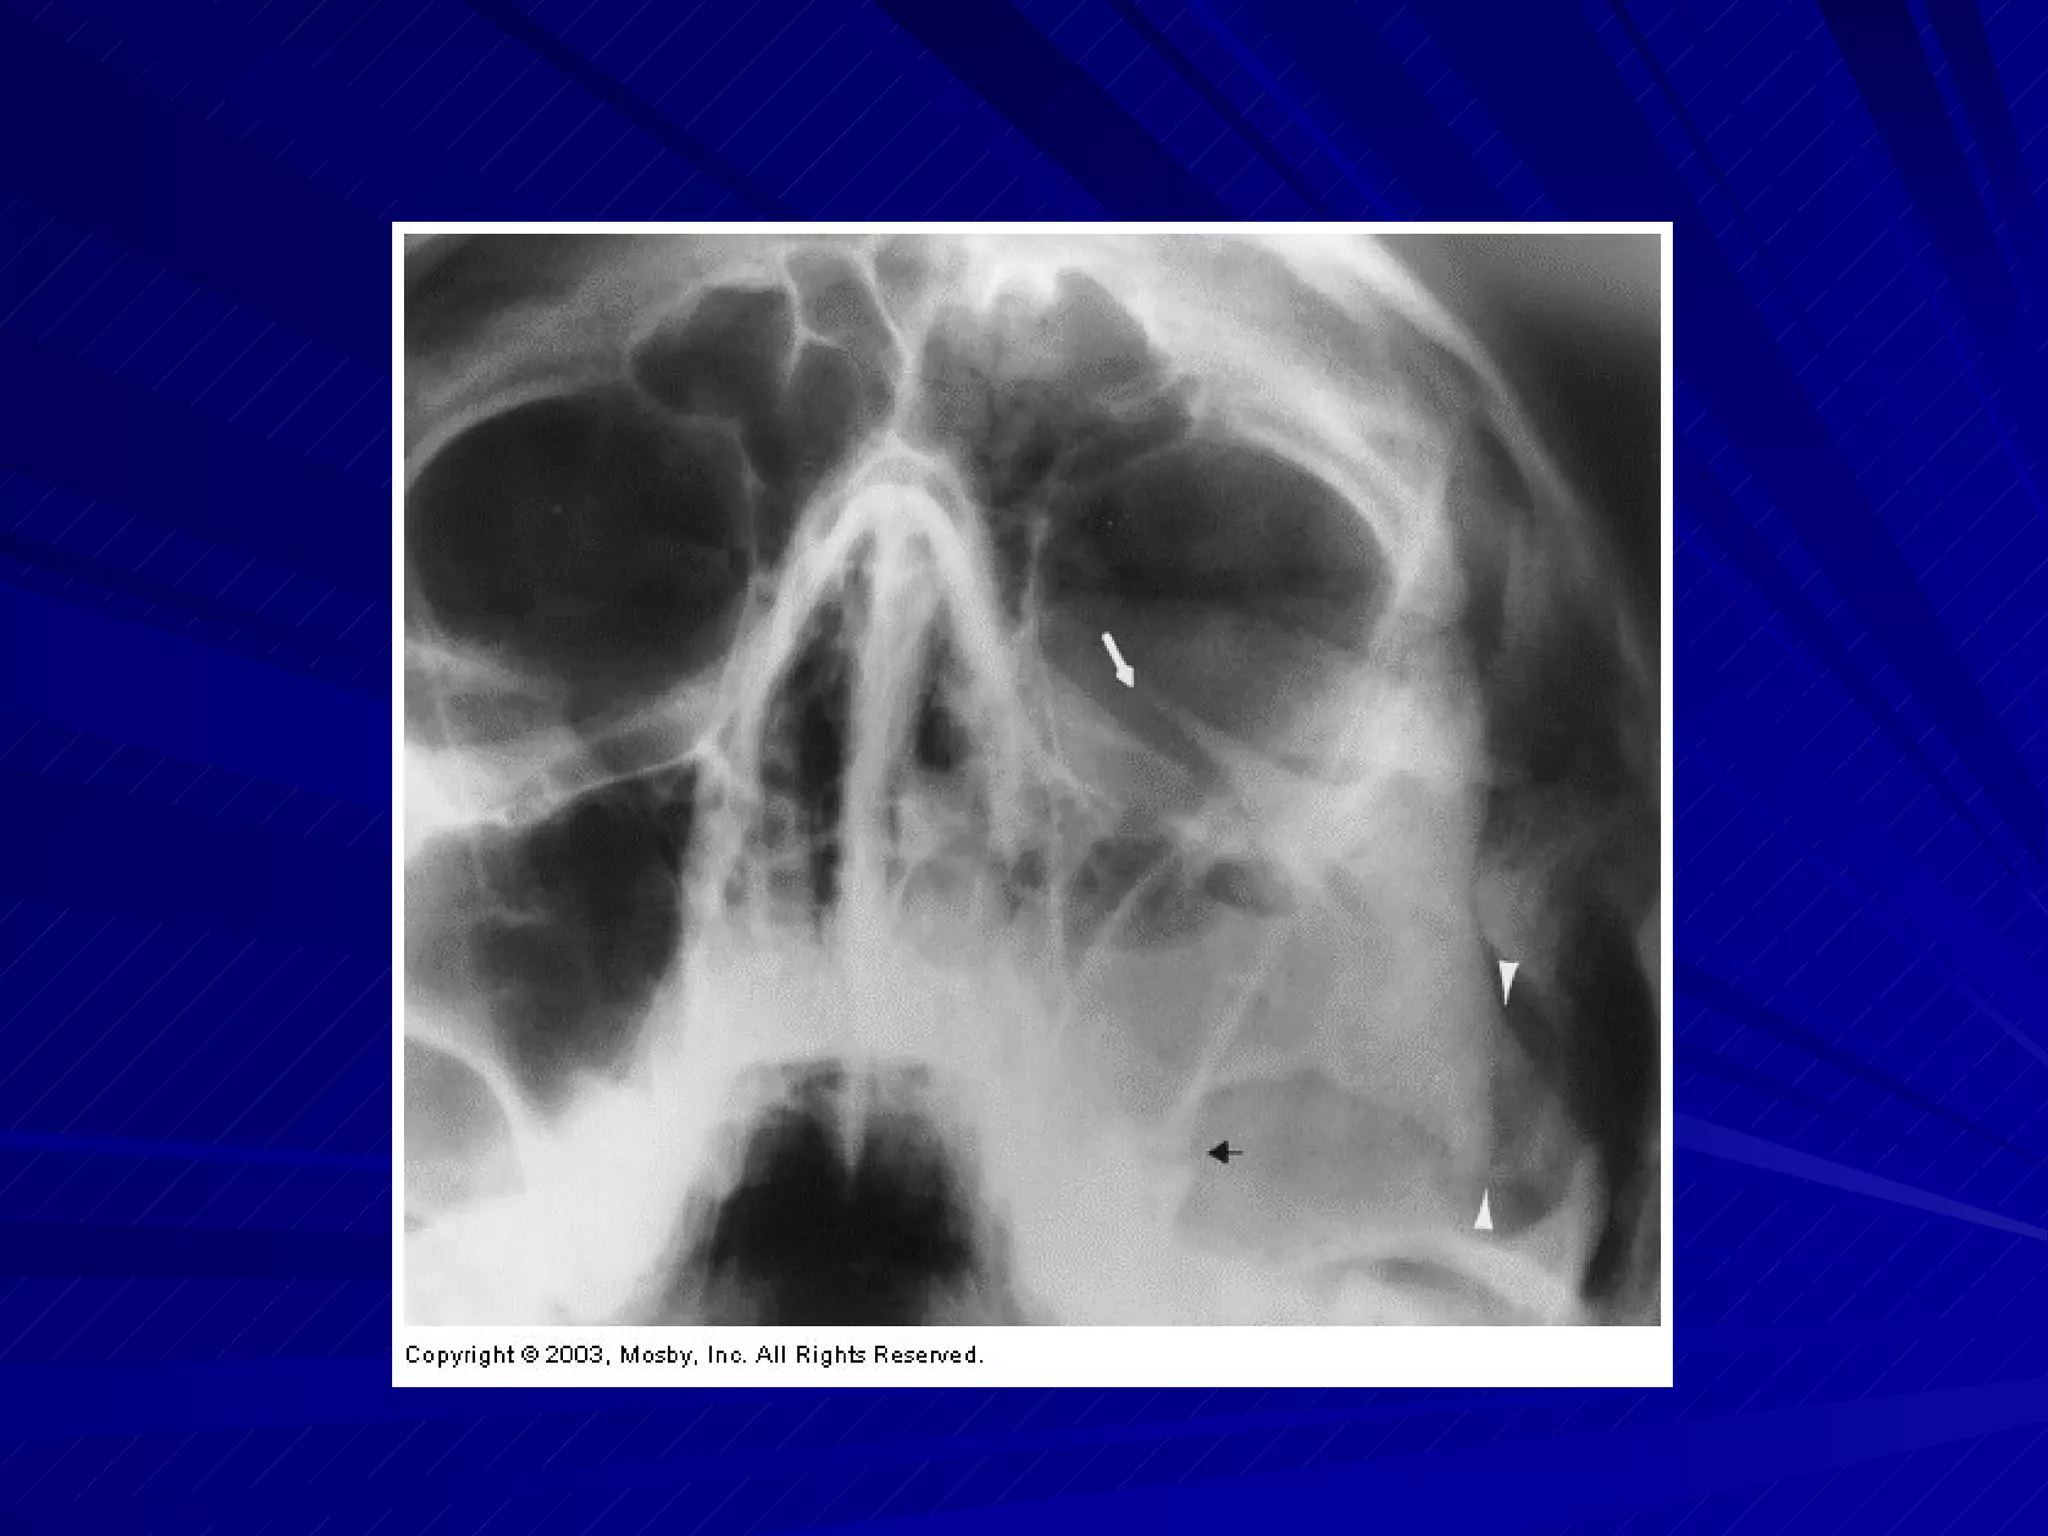

Facial Bones Patients with facial bone injuries are often referred to CT first Anticipate profuse bleeding and use universal precautions

Facial Bones Patientswith facial bone injuries are often referred to CT first Anticipate profuse bleeding and use universal precautions